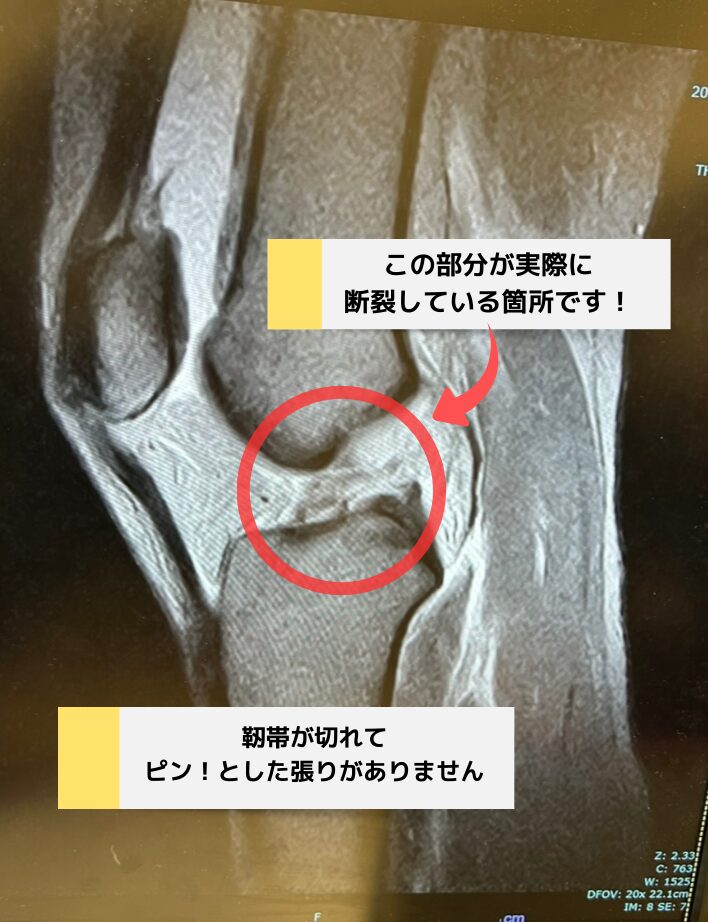

↓これは私が実際に前十字靭帯を切った直後のMRIの画像です

完全断裂になると靭帯は張りが出ないためMRIでもはっきりと確認することができました